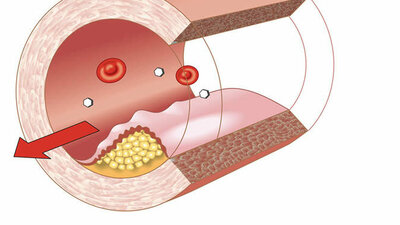

Arterienverkalkung

Arterienverkalkung

Arteriosklerose – gefährlicher Engpass

Gefäßverkalkung kann zu Herzinfarkt, Schlaganfall und anderen Durchblutungsstörungen führen. Mehr zu Ursachen, Therapie und Vorbeugung. zum Artikel